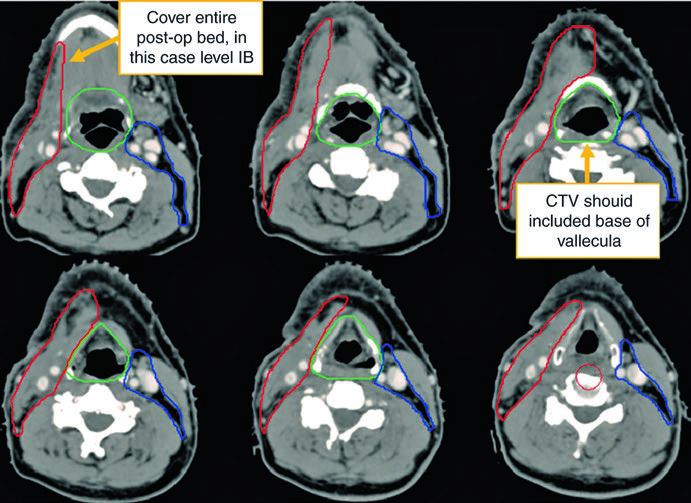

O primeiro caso ilustra um homem de 62 anos com primário oculto TxN2a, submetido a tonsilectomia bilateral e esvaziamento cervical direito, que revelou um único linfonodo de 4,6 cm no nível II.

Observe a diferença entre o delineamento no pescoço operado (ipsilateral) e o contralateral. O CTV66Gy (vermelho) cobre o leito cirúrgico de alto risco; o CTV54-60Gy (verde) cobre as mucosas faríngeas em risco de abrigar o primário; e o CTV54Gy (azul) cobre o pescoço contralateral profilaticamente. Essa assimetria reflete o princípio de escalonar a dose conforme o risco real.

A visualização em cortes sagitais (Fig. 10.2) é particularmente útil para confirmar a extensão craniocaudal correta dos volumes de mucosa — nasofaringe, orofaringe e laringe/hipofaringe — e assegurar que não haja lacunas entre os CTVs adjacentes. O isocentro radiográfico serve como referência geométrica para o planejamento.